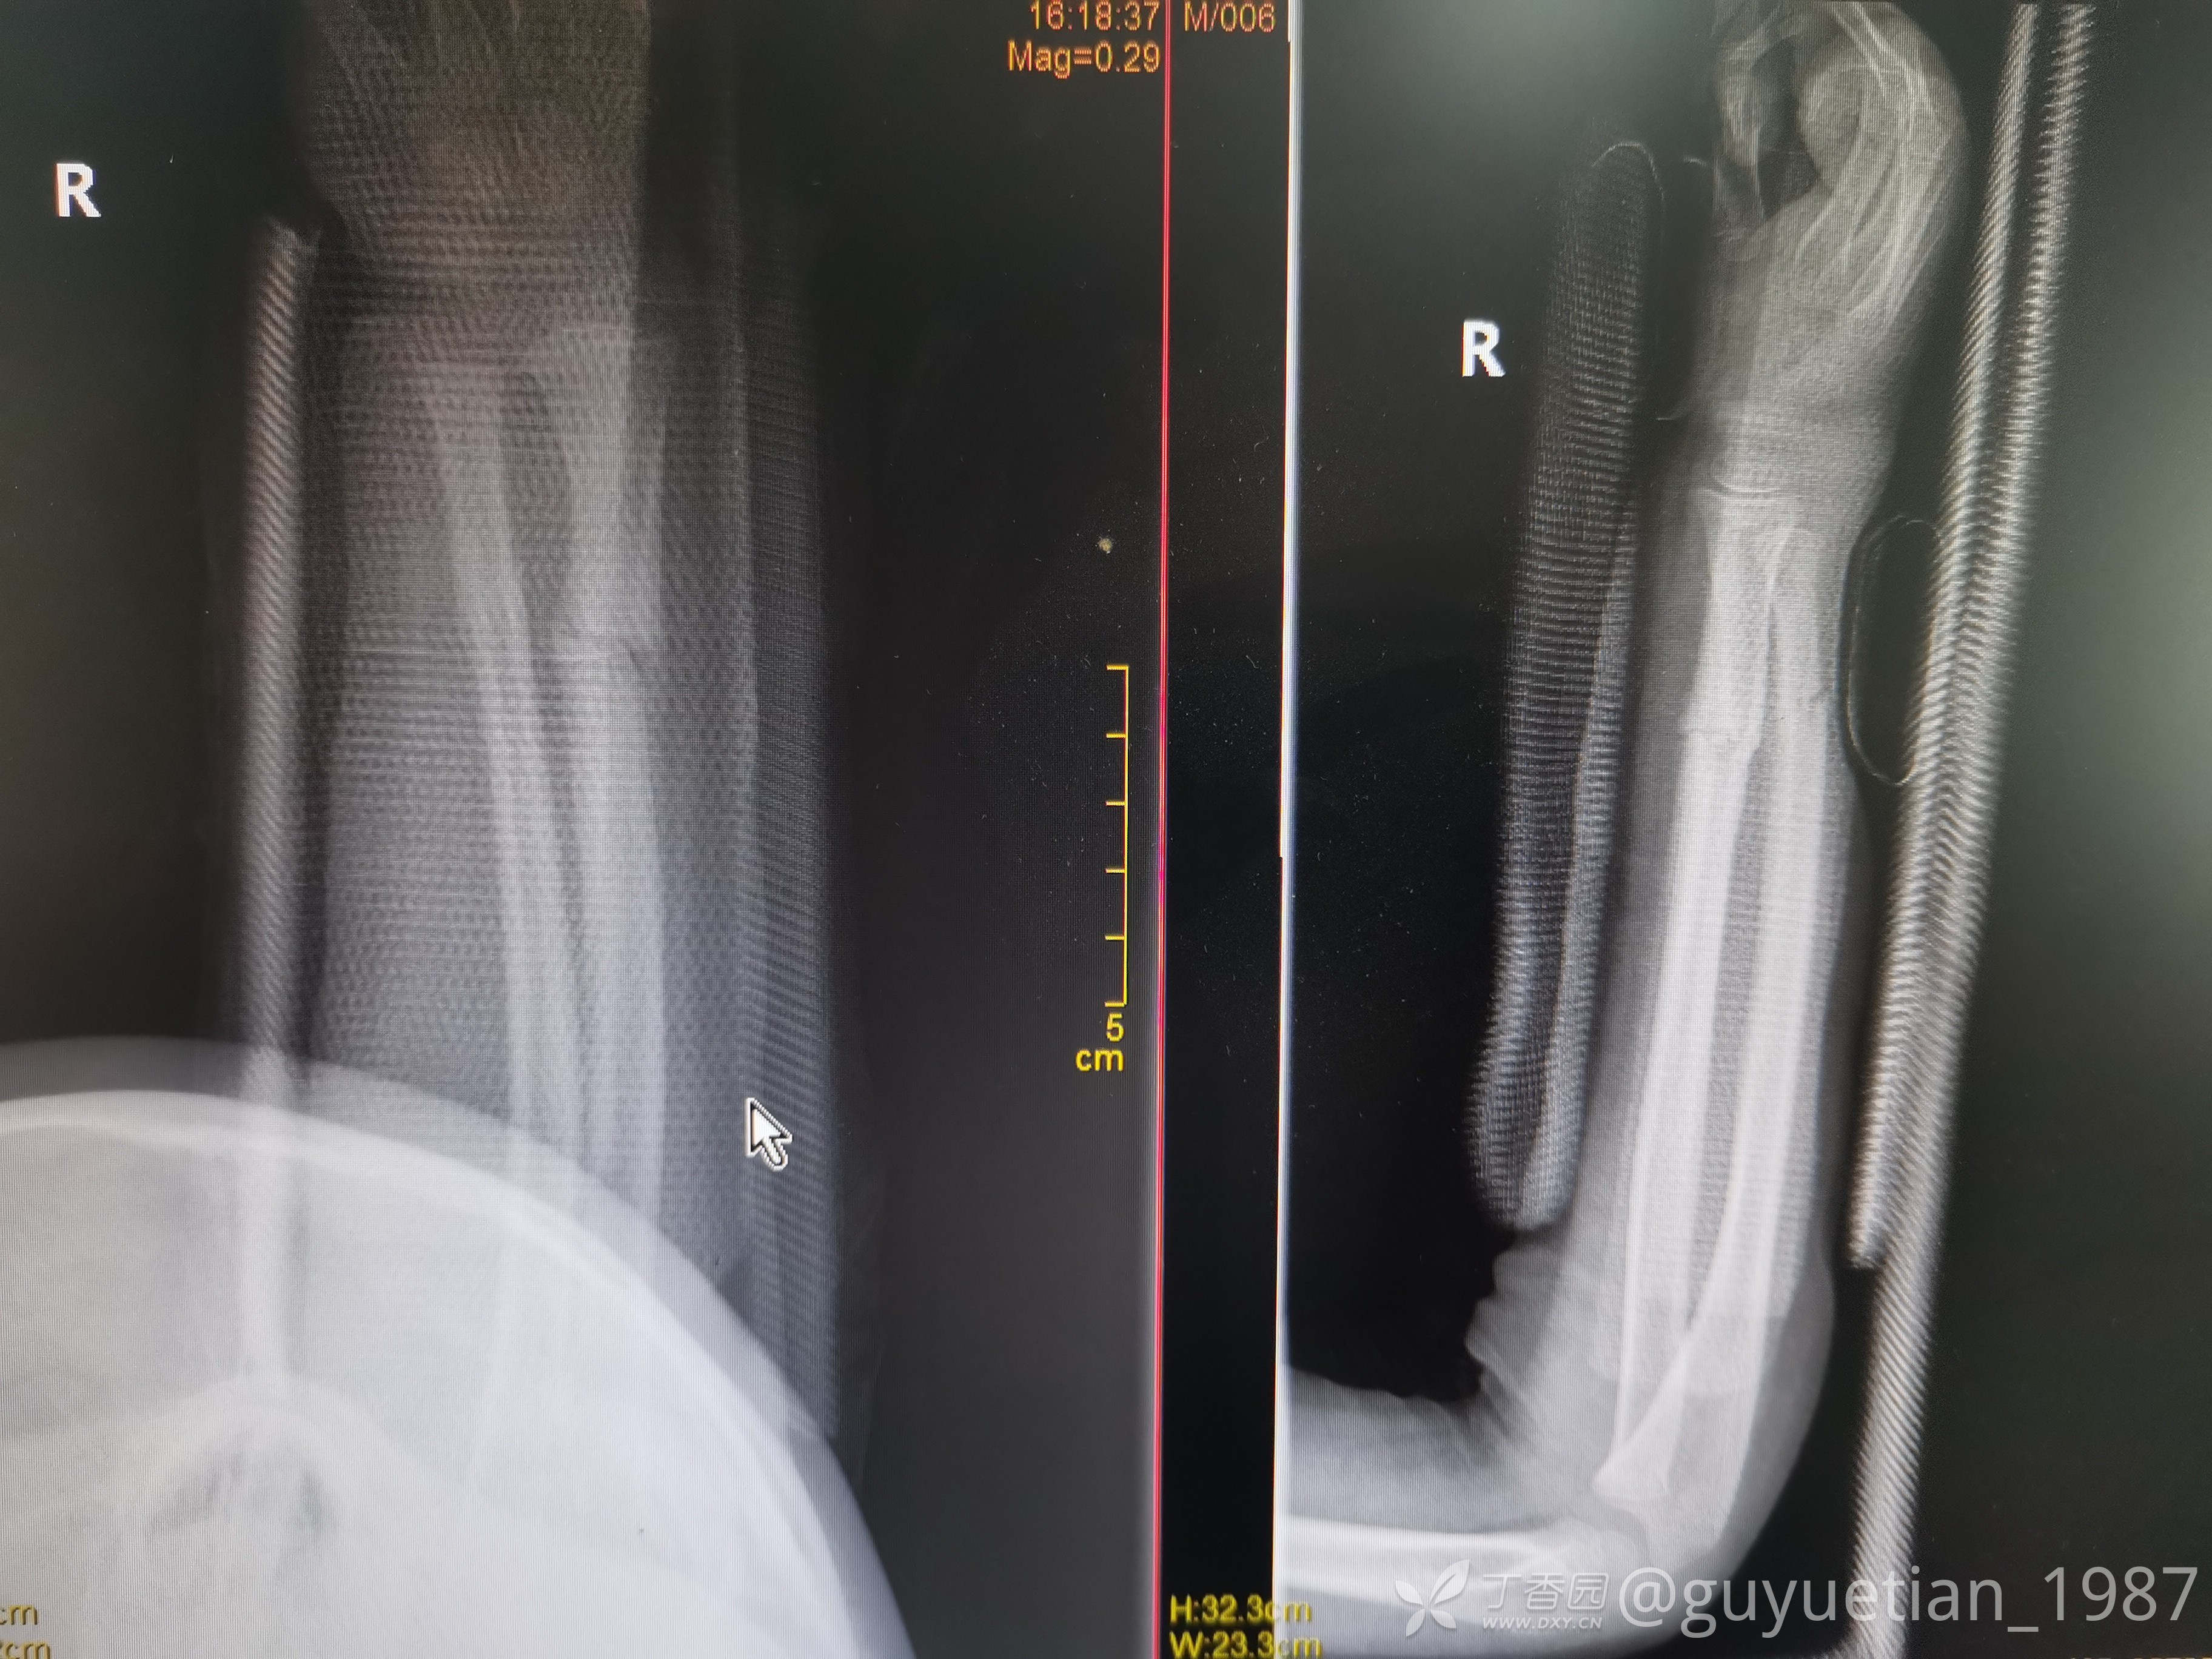

7周后复诊

2月余复诊,基本完全塑形